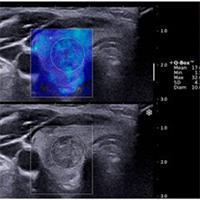

• الاستوگرافی اولتراسوند(Ultrasound elastography): این متد با نام فیبرواسکن نیز شناخته می‌شود و متداول‌تر است. این روش مانند سونوگرافی است و از امواج صوتی برای تشخیص فیبروز و کبد چرب استفاده می‌کند. بنابراین دارای پروب است.

• MRE (الاستوگرافی رزونانس مغناطیسی): این روش ترکیبی از MRI و سونوگرافی است. در این روش نمای بصری از کبد روی مانیتور نمایش داده می‌شود که میزان فیبروز کبدی را مشخص می‌کند

کبد در قسمت بالایی شکم و زیر استخوان‌های قفسه سینه قرار دارد. بنابراین برای الاستوگرافی، پروب باید روی این ناحیه قرار گیرد. بیمار باید به پشت روی تخت مخصوص دراز بکشید. سپس پزشک قسمت مورد نظر را آغشته به ژل می‌کند. سپس پروب الاستوگرافی را که با نام پروب فیبرو اسکن نیز شناخته می‌شود، روی ناحیه مورد نظر قرار می‌دهد. در نهایت نتایج روی مانیتور نمایش داده می‌شود و قابل پرینت خواهد بود. پزشک نیز با توجه به نتایج تحلیل لازم را انجام می‌دهد. این نتایج وجود کبد چرب، سیروز، فیبروز و سایر بیماری‌های کبدی را نشان می‌دهند.